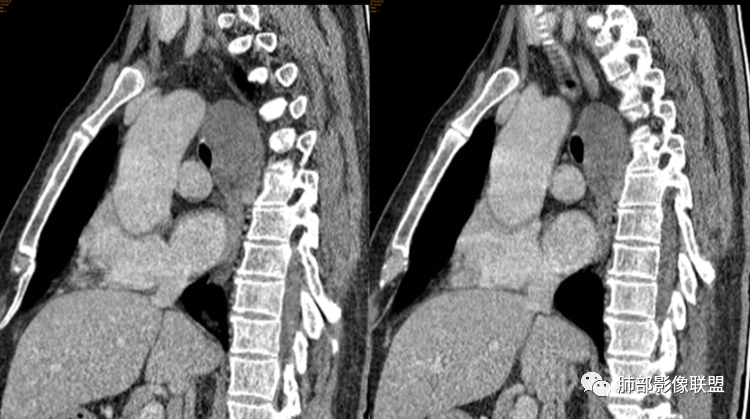

男性,43岁,体检发现后纵隔占位,边缘光整,CT示密度均匀,周围组织受压移位,无钙化囊变及脂肪组织,增强未见明显强化。MRI:T1示肿块信号较肌肉高,T2不均匀高信号。考虑为良性病变,第一是神经节细胞瘤,其次是支气管源性囊肿。

后纵隔占位,椭圆形,边缘不规则,CT低密度,MRI长稍长T1稍长T2信号,增强扫描未见强化,支气管受压。囊性病变,考虑支气管囊肿(常见,T1WI稍低“比水高”T2WI稍高,可能与其内含有粘液或蛋白有关);鉴别淋巴管囊肿(更软塑性性更大,接近纯水MRI信号长T1长T2,受周围挤压更明显,变形。);神经节细胞瘤瘤(增强可有轻度渐进性强化,也可不强化,关键是不常见),还有就是神经源性囊肿与肠源性性囊肿。

后纵隔占位;食道向右侧推移,病变质软,CT平扫密度均匀,边缘清晰光整,MRI 稍长T1,长T2高,脂肪抑制高信号。考虑纵隔良性囊性占位。先考虑支气管囊肿。其它类囊肿待除外。

定位,后纵隔囊性占位,边界清楚,内部密度均匀,张力高,囊壁均匀,周围结构受压,增强后无强化。MRI:长T2信号。考虑良性囊性病变,支气管囊肿、淋巴管囊肿。

(2)囊液密度均匀,根据性质的不同而呈不同密度,可为近似水样密度,也可为较高密度,因为囊壁分泌粘液,所以囊内密度一般高于其他纵隔囊肿,CT值多大于20HU甚至超过60HU;

(3)若囊肿内密度较高时与实性肿块鉴别较为困难,增强扫描囊液无强化为鉴别要点;但是囊壁因为含有平滑肌成份,所以可能环形强化;如果病灶合并感染,病灶壁也会明显强化。

(5)张力不高时可以形态柔顺,成份复杂时可以密度较高,但内部不会强化。